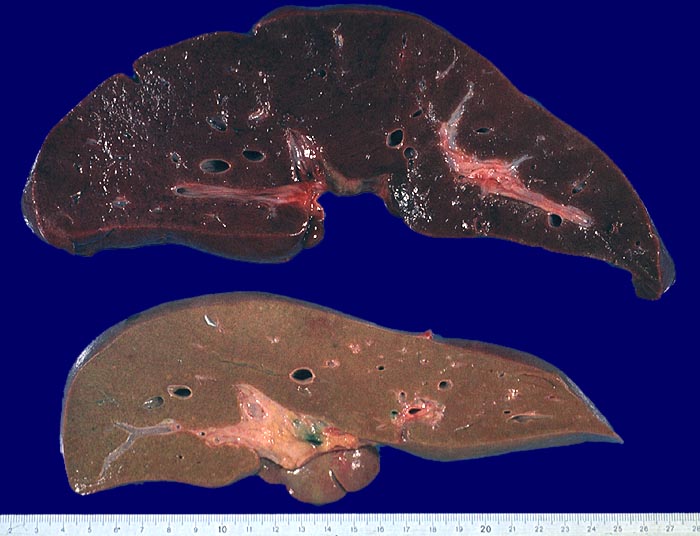

PathoPic – image database / PathoPic ID 2767 - fulminante Hepatitis (unten)

fulminante Hepatitis (unten)

Verkleinerung und Gelbverfärbung des Organs. Oben zum Vergleich eine normale Leber.

Knollenblätterpilzvergiftung.

Massiver Leberzellzerfall bei der nekrotisierenden Form der akuten Hepatitis (Hepatitis B 0.5%, Hepatitis A 0.2-0.4%, Hepatitis C 0.5%) oder bei medikamentös toxischem Leberschaden (Knollenblätterpilzvergiftung). Ausgedehnte Parenchymnekrosen ohne nennenswerte mesenchymale Reaktion. Die fulminante Hepatitis endet bei 75% mit dem Tod.